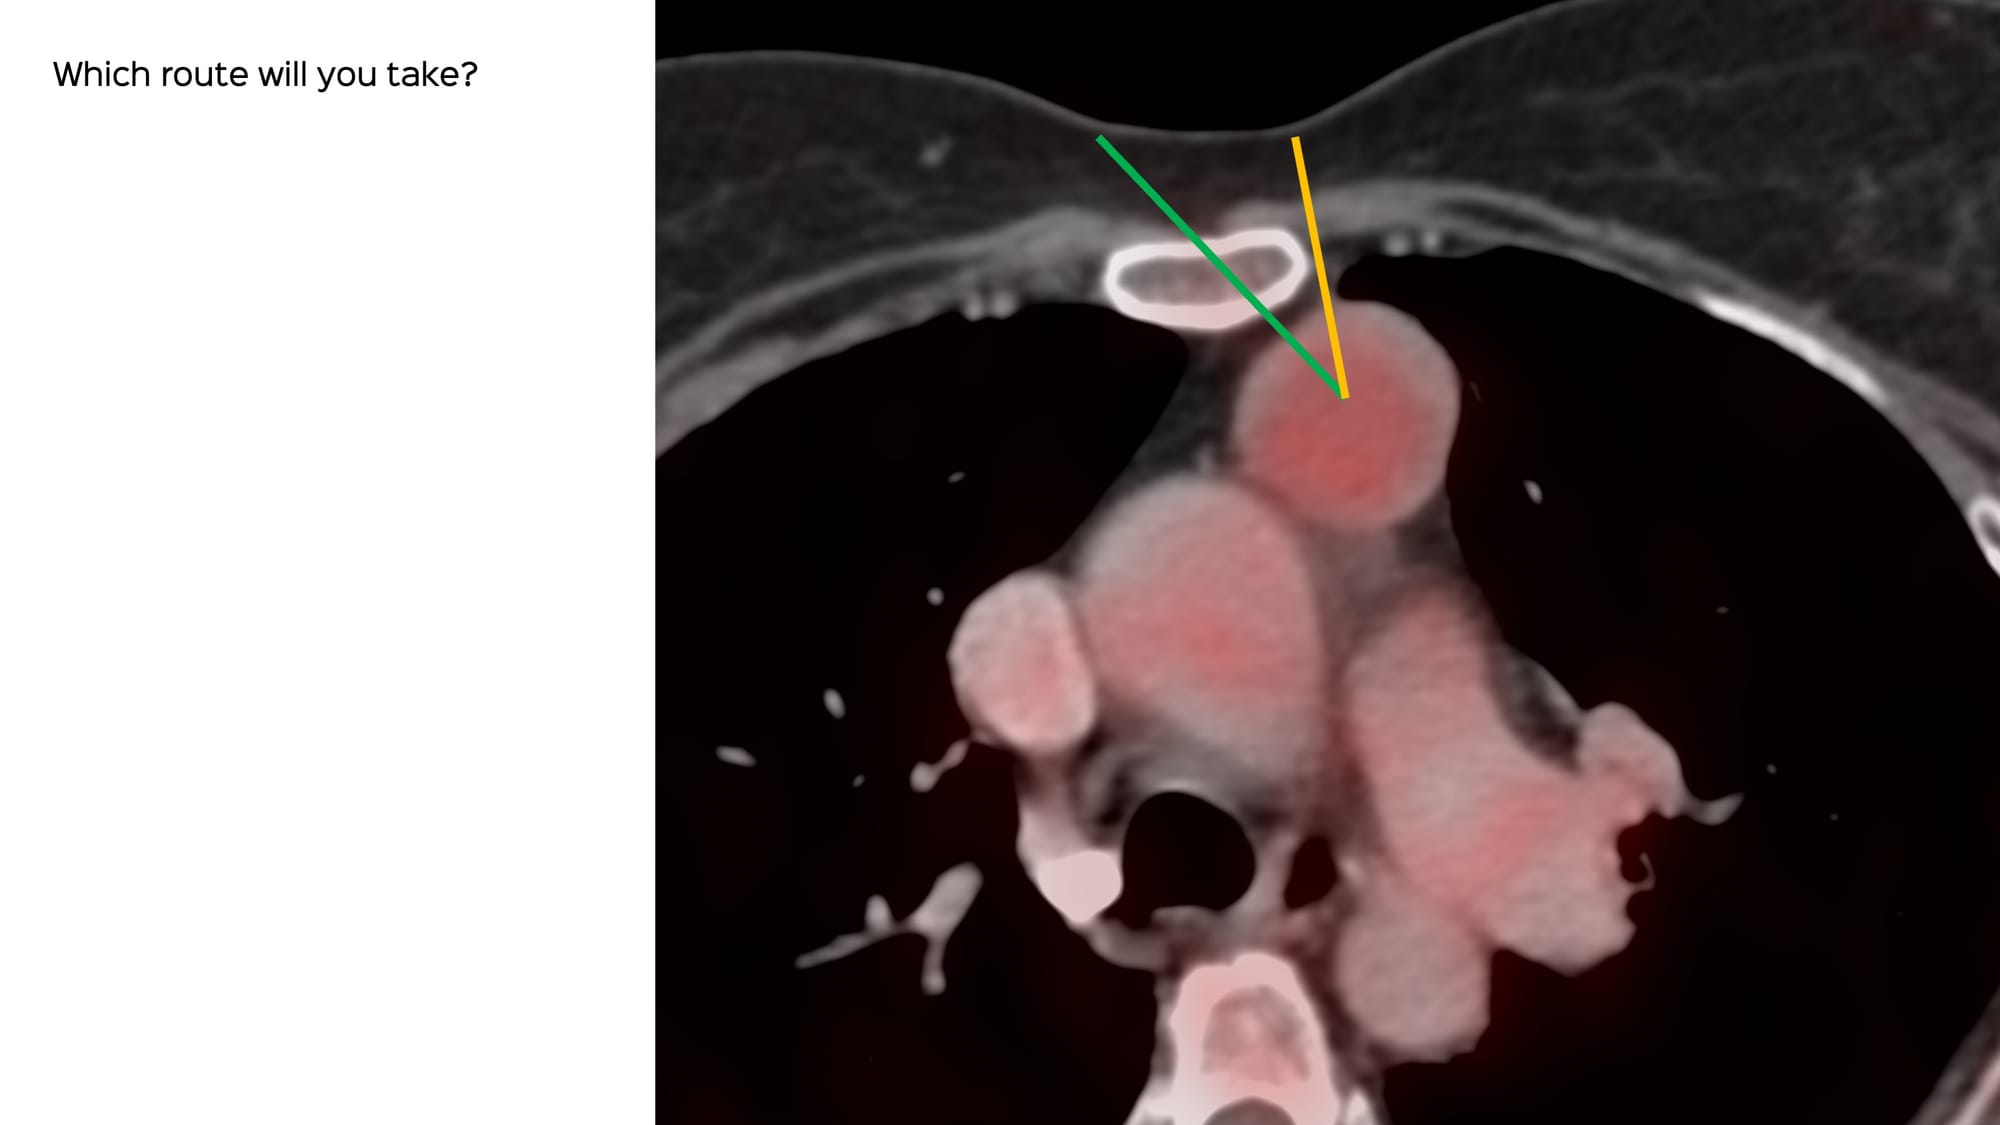

- Will you biopsy?

- If so, then which route?